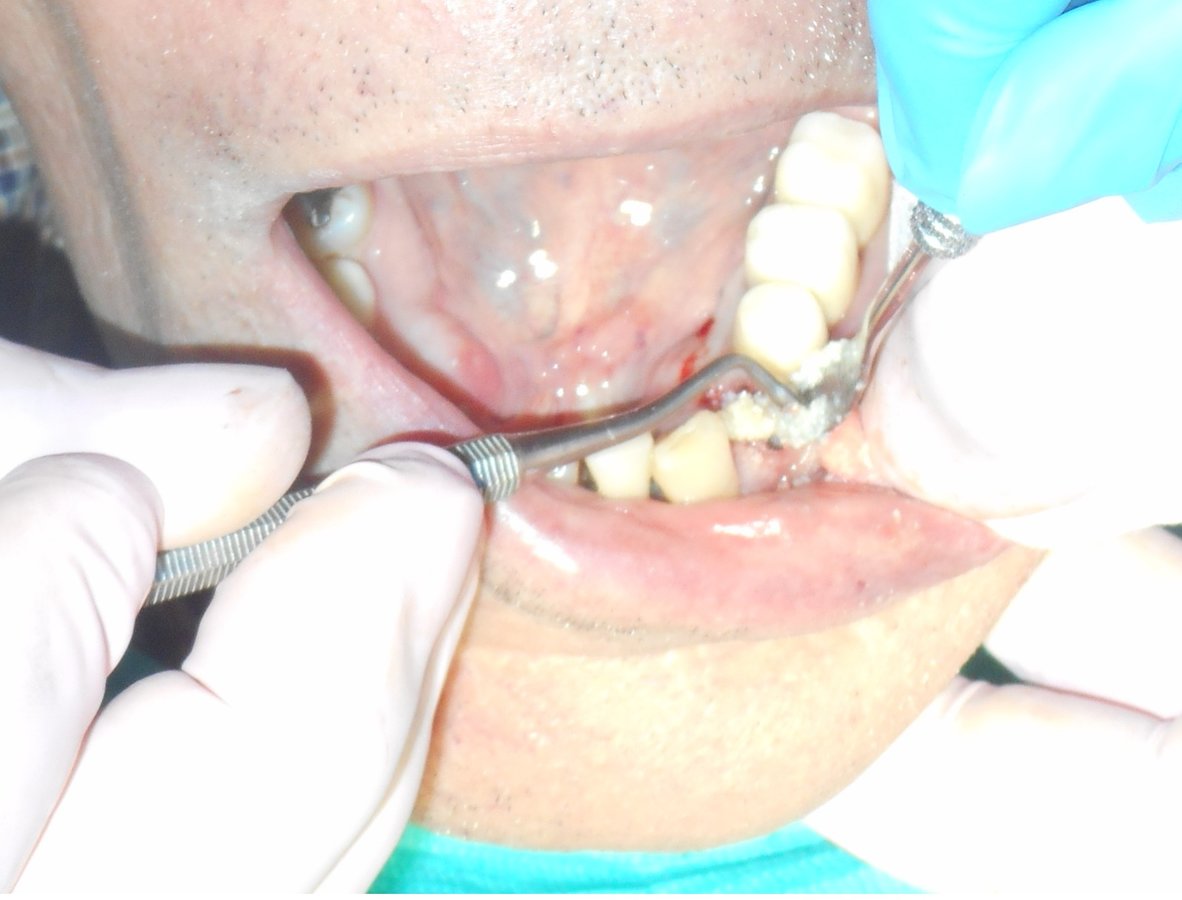

About Alpha Dental Implant Center Dental care can be affordable. See what we can do for you. FREE exam and estimate. We are in Nuevo Progreso Mexico, The Safest border town in Texas. Just across the border of Weslaco, Texas., We are a Full-Service Dental Clinic, But We Specialize in Dental Implants. All done, By a Qualified Dentist in his field, With Quality Materials, at a Reasonable Price. 2019 Harvard Dental Boston Internationa... (Show more)

| Bone Graft | $300 |